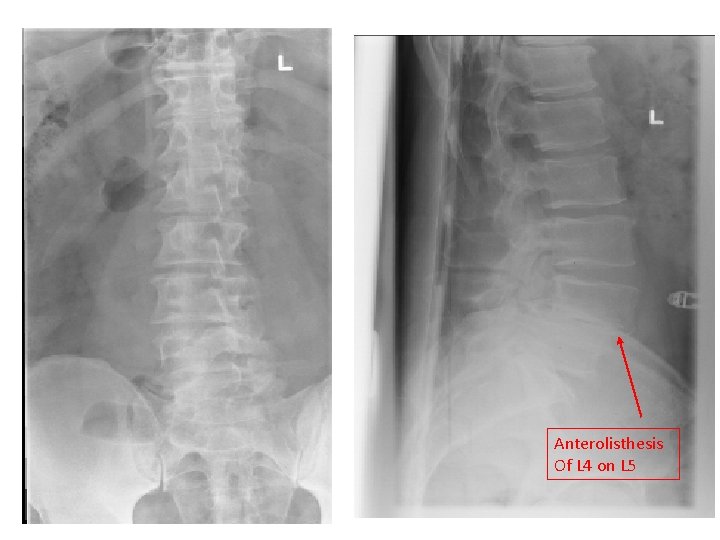

Anterolisthesis Of L 4 on L 5